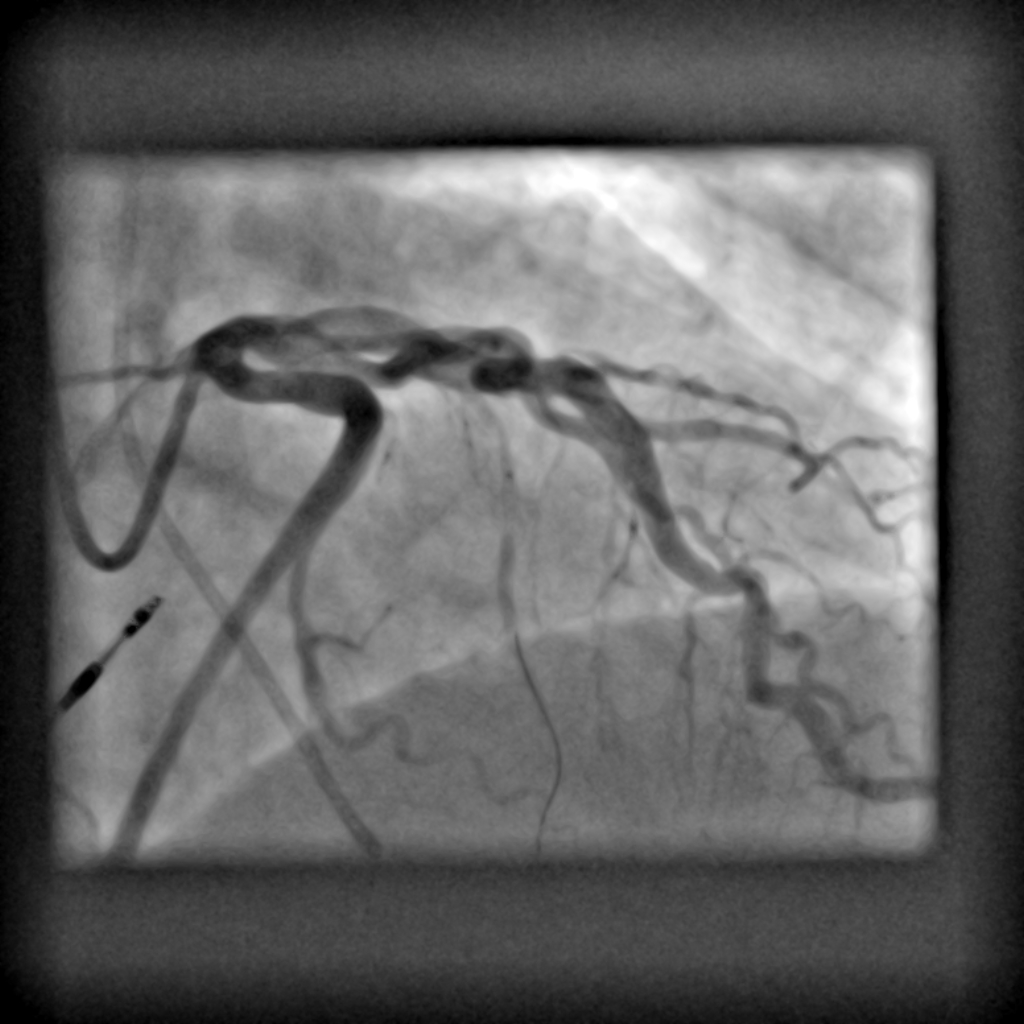

Die diagnostische Koronarangiographie ist ein etabliertes Verfahren zur genauen Beurteilung der Herzkranzgefäße. Sie wird vor allem eingesetzt um Durchblutungsstörungen der Herzkranzgefäße (so genannte Koronare Herzkrankheit) zu erkennen. Die Untersuchung liefert präzise Informationen über den Zustand der Gefäße und dauert circa 20-30min. In der Regel ist eine örtliche Betäubung ausreichend. In vielen ällen kann direkt im Anschluss die notwendige Therapie - etwa die Aufdehnung einer Engstelle oder das Einsetzen von Stents - erfolgen. Damit stellt die Herzkatheteruntersuchung einen wichtigen Baustein in der modernen kardiologischen Diagnostik und Therapie da.

- Linksherzkatheter (inkl. Ventrikulographie)

- Rechtsherzkatheter (Ruhe und Belastung) zur Beurteilung der intrakardialen Druckverhältnisse und der Lungendrücke